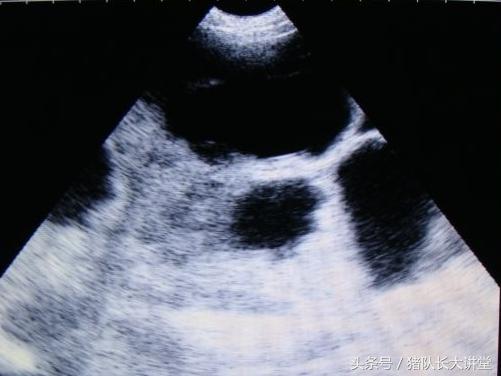

中间的黑球是初期胚胎

A、可以较为准确的测出是不是有小猪,具体使用办法,根据说明使用,大家也可以提出问题;关注,一般你检测有的就是有了,单是检测没有的时候应该多视察;